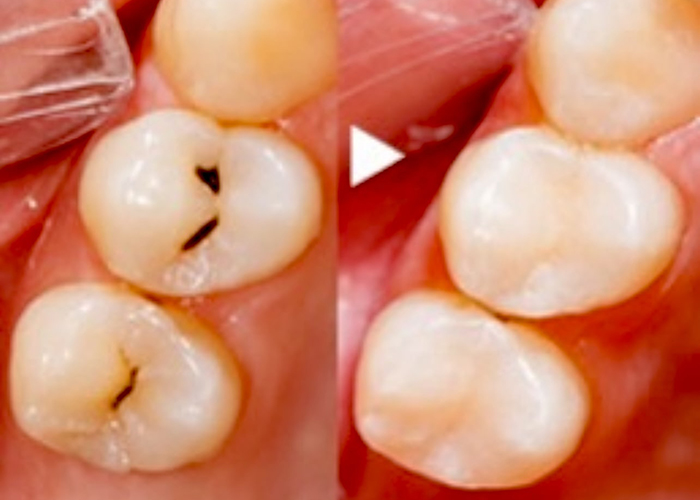

虫歯が疑われたが削らずに済んだ例

視診では歯間部が黒く透けており虫歯が疑われ治療が必要そうな状態 |

レントゲンでは虫食い状に黒く写ってはないので深く虫歯は進行してはいないと判断した |

レーザー診断にて数値が「40」だったため『初期虫歯』と判断し、削らず経過観察とした。 |

このように数値で虫歯の進行状況がわかるため、なるべく削らない治療が可能です。

当院では61以上の数値で治療が必要と判断します。

視診では歯間部が黒く透けており虫歯が疑われ治療が必要そうな状態

レントゲンでは虫食い状に黒く写ってはないので深く虫歯は進行してはいないと判断した

レーザー診断にて数値が「40」だったため『初期虫歯』と判断し、削らず経過観察とした。